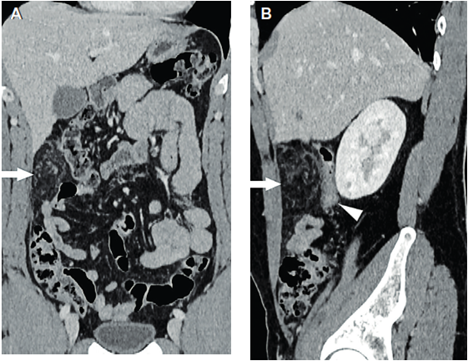

Ante la persistencia del dolor se decidió complementar los estudios con tomografía computarizada de abdomen con y sin contraste intravenoso (Figuras 1 y 2) donde se aprecia infarto del omento, para lo que se inicia tratamiento médico conservador. Luego de 24 horas aumenta el dolor abdominal, por lo que se realiza laparoscopia exploradora. En el intraoperatorio, se confirma necrosis del sector superior derecho del epiplón mayor; se realiza la resección con ligasure® (Figura 3). Tuvo buena evolución posoperatoria, dando de alta a las 48 horas. La anatomía patológica confirmó el diagnóstico de infarto omental.